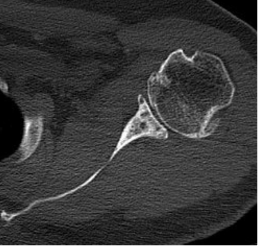

BH is a right hand dominant 70-year-old female, who is retired and moderately active. She presents with 8 months of progressively worsening left shoulder pain affecting her ADLS, sleep and recreational activities. She is 10 years s/p a right anatomic total shoulder arthroplasty. Radiographs and advanced imaging reveal glenohumeral joint advanced degenerative joint disease with an intact rotator cuff. Preoperative planning reveals a native 3 degrees of retroversion with 0 degrees of inclination. As she was extremely happy with the fully functional contralateral shoulder she has enjoyed for the past decade, she was interested in the same solution – an anatomic total shoulder arthroplasty.

At age 70 secondary rotator cuff tears following anatomic total shoulder arthroplasty must be weighed against complications and postoperative function of reverse shoulder arthroplasty [3]. Exactech Predict+ was able to demonstrate comparable postoperative function, scores, pain, and complications. A decision was reached to proceed successfully with an anatomic total shoulder arthroplasty.